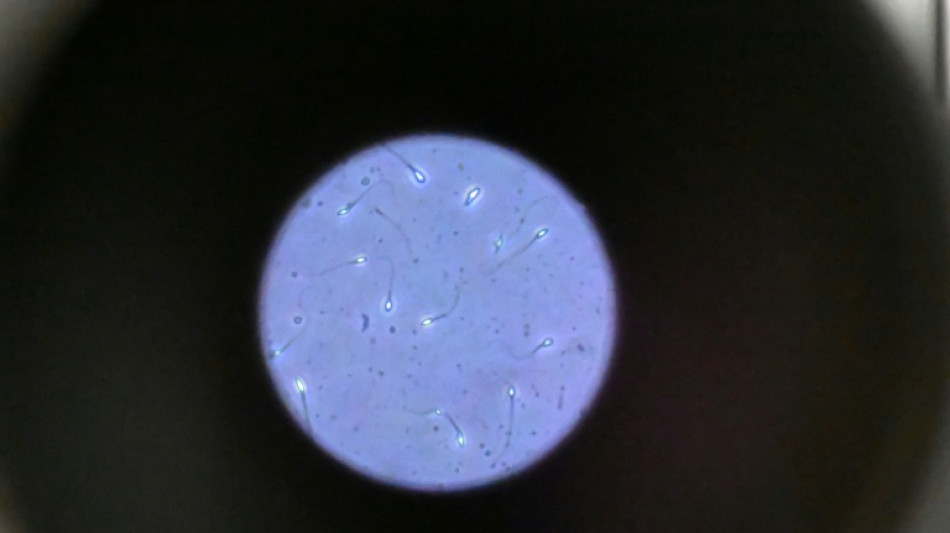

Un mort dans une explosion considérée comme "terroriste" devant une clinique en Californie

L'explosion d'une bombe a fait un mort samedi devant une clinique spécialisée dans la procréation médicalement assistée (PMA) en Californie, la police fédérale considérant qu'il s'agit d'un acte terroriste.